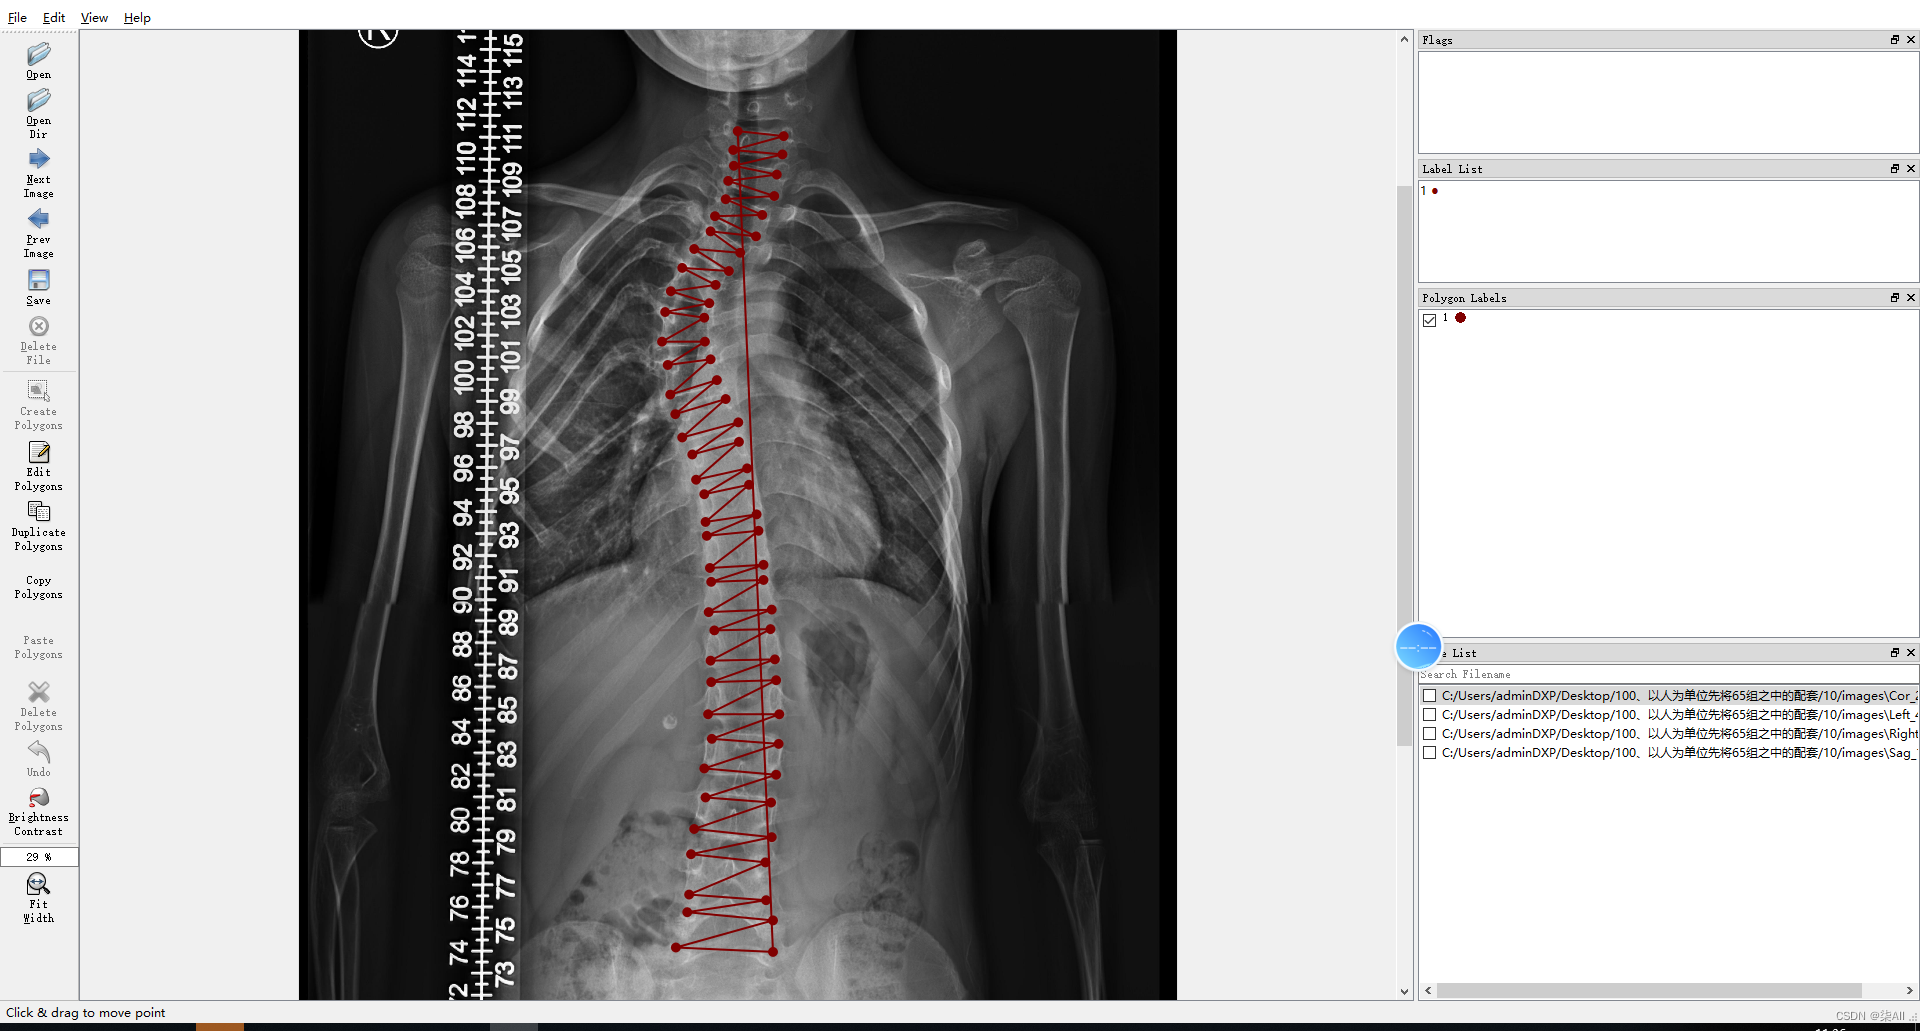

2、开始标注(以冠状位为例,其他方位是一样的操作,视频教程)

冠状位关键点标注教程

3、冠状位标注结果

4、标注过程注意事项